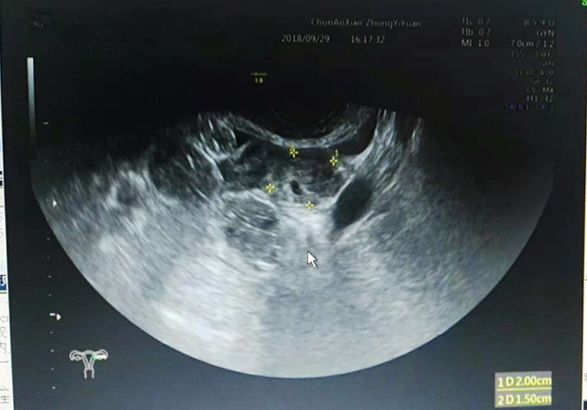

近日,一名38岁女性患者,1个月前在某医院行人流术后出现阴道出血,腹痛,怀疑人流后残留来县中医院妇科门诊就诊。经妇产科仔细检查,结合尿HCG700mIU/ml,超声检查左附件区混合回声团块,最终考虑并非人流后残留,而是存在宫外孕现象,当即给予收住入院。这种宫内孕合并宫外孕的病例非常少见,幸好中医院妇产科临床医生谨慎,超声医生检查仔细,手术及时,一起合作解除了病魔。

宫内孕合并宫外孕十分少见,仔细询问该患者病史才得知,该患者已经有双胞胎宝宝,家族有双胞胎基因。此次意外怀孕也是双胞胎,一个在宫内,一个却是在宫外。

复合妊娠是指同时发生在2个或以上种植部位的妊娠,以宫内外复合妊娠常见,在自然妊娠中罕见,发生率约1/30000,随着辅助生殖技术广泛开展,发生率明显增高,达1%左右。宫内外复合妊娠中最常见类型为宫内合并输卵管妊娠约占88.2%,超声是主要诊断方法。